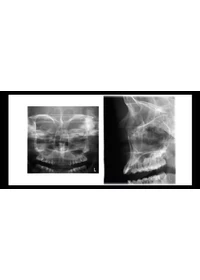

Gyermek üzemmód az optimális gyermekgyógyászati képalkotásnál

Gyermek üzemmódban a leképezési terület és az expozíciós értékek csökkennek minden programban, és a fokális réteg is szűkíthető a panorámaprogramban. A beteget érő dózis jelentősen csökken.